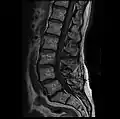

MRI lumbar spine with degeneration, post-hemilaminectomy L4-5 (sagittal FAST STIR)